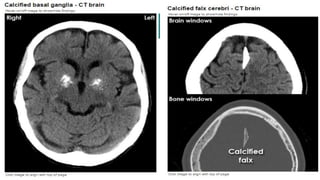

Normal calcification

The basal ganglia

Pituitary fossa

The pineal gland